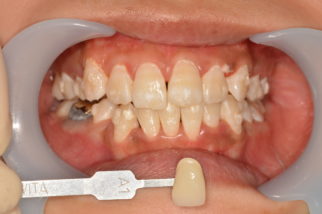

まずこちらが施術前

こちらが施術後

まだ1回目ですがだいぶ白くなりました(‘ω’)ノ